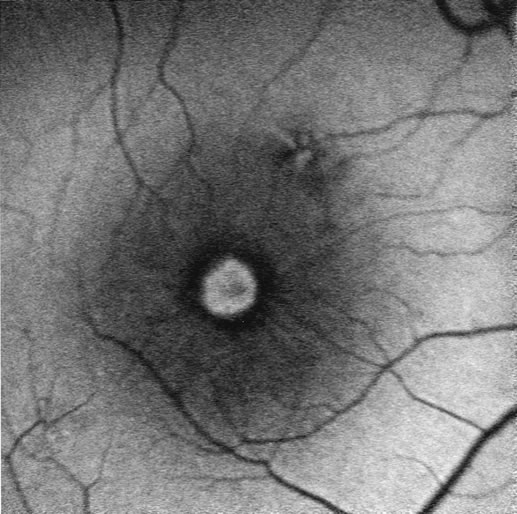

DIAGNOSIS Age-related macular degeneration (AMD) may be divided into two types. Nonexudative (“dry”) AMD has several morphologic forms, including “hard” discrete drusen, shallow retinal pigment epithelial detachments associated with thickened Bruch's membrane (“soft” drusen), and geographic atrophy (GA) of the retinal pigment epithelium (RPE).3 On FA the area of GA appears hyperfluorescent for window defect from the early frames of the angiogram, with late staining of the underlying sclera (Fig. 1). However, these pathologic changes can usually be assessed by clinical examination, and FA is generally not necessary to diagnose nonexudative AMD. An exception is cuticular drusen, which may appear clinically as a subtle disturbance of the RPE; FA reveals multitudes of small, discrete drusen described as “stars in the sky” (Fig. 2). The second type of AMD, which is associated with soft drusen, is known as exudative (“wet”) AMD. It is due to a choroidal neovascular membrane that has incompetent vessels resulting in detachments of the RPE and the neurosensory retina. Consequently, in patients with a large RPE and/or serous neurosensory detachment, FA is often necessary to rule out a choroidal neovascularization (CNV). In general, a small pigment epithelium detachment (PED) and a larger neurosensory detachment overlie CNV, while the opposite is generally the case in a nonexudative PED. Additionally, CNV often presents as a “notched” PED (Fig. 3).4 The presence of subretinal blood or pigment at the border of a PED strongly indicates that the detachment is exudative in origin (Fig. 4). Similarly, a rip in the RPE generally reflects subretinal fibrosis from a CNV (Fig. 5 and 6). The diagnosis is more difficult in patients who have a chronic, organized PED. Such a lesion may be due to either nonexudative AMD or to an organized, fibrotic CNV. Clinically and angiographically, it may be impossible to distinguish between these two conditions. In most cases, however, FA does assist in making the diagnosis.